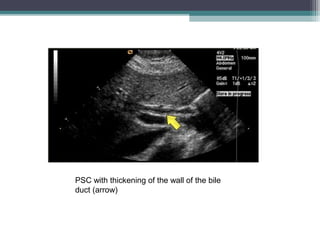

• Ultrasound

• Ultrasound is able to demonstrate both the changes of cirrhosis and

irregularity of bile duct calibre.

• USG diagnosis is difficult because bile duct dilatation in PSC is minimal due

to surrounding fibrotic reaction

PSC with thickening of the wall of the bile

duct (arrow)